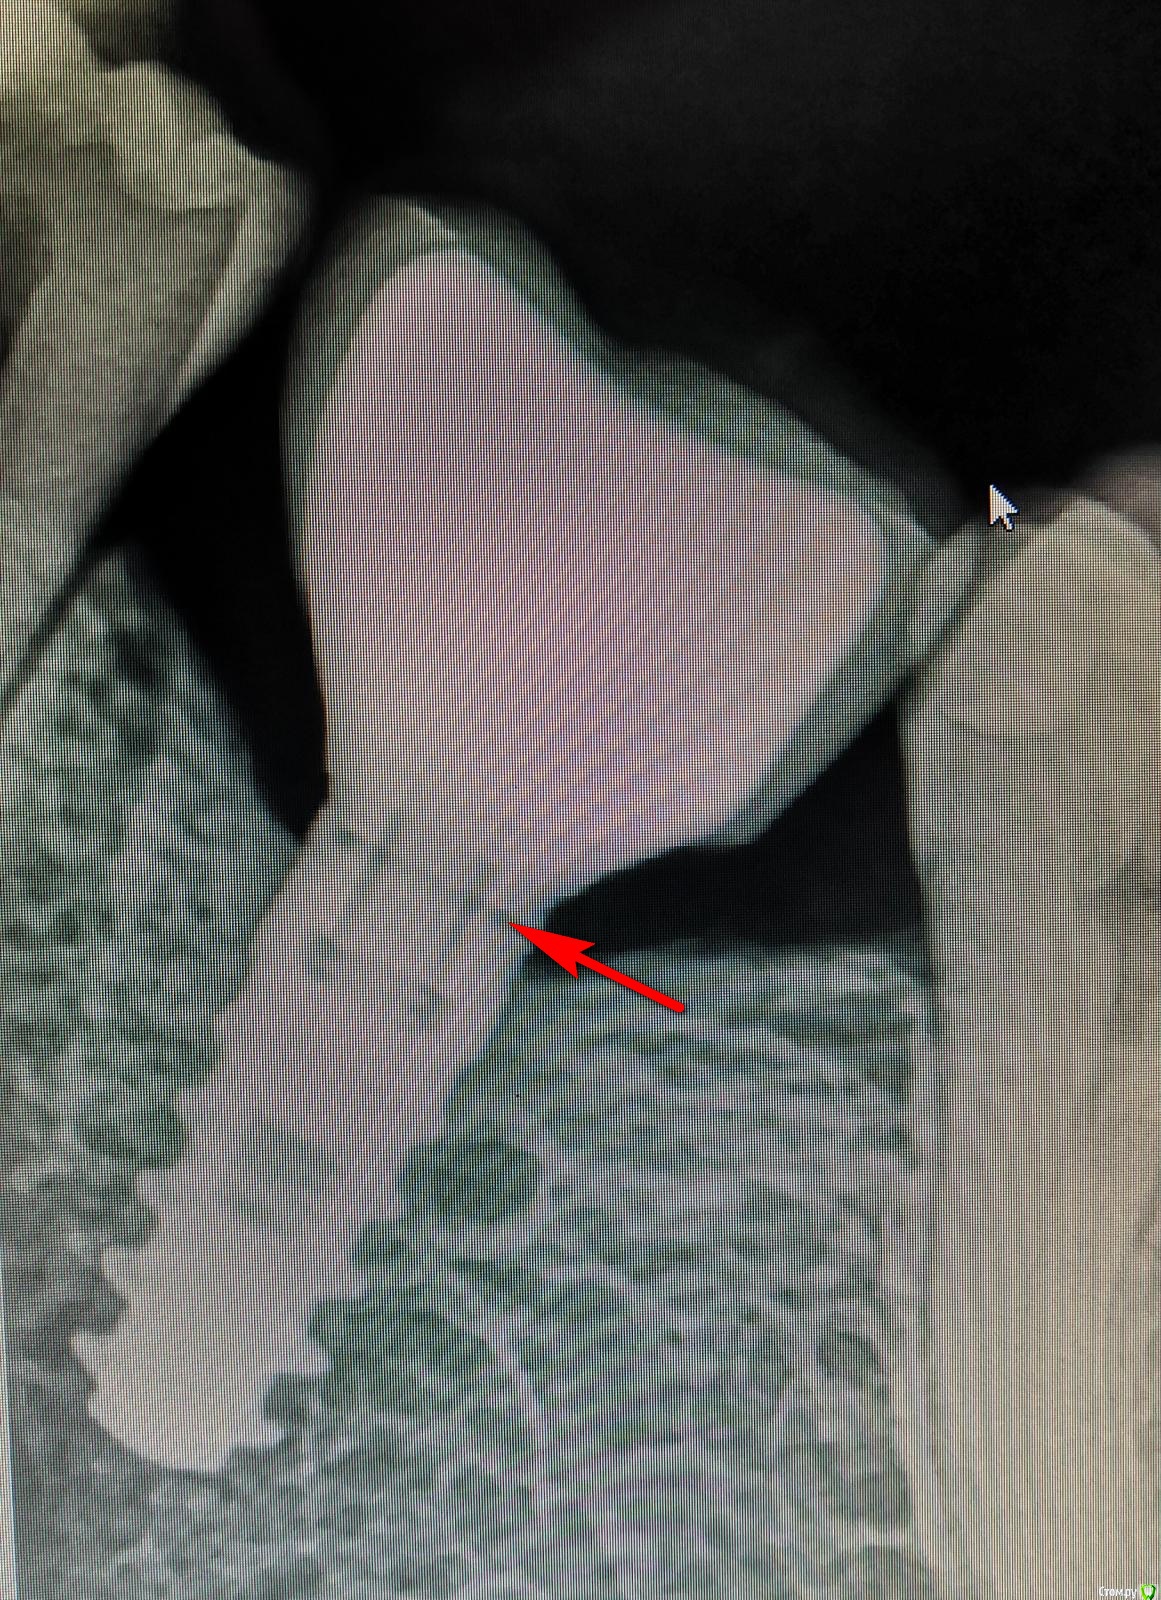

Невероятный Алк2 Опубликовано 30 января, 2019 Автор Поделиться Опубликовано 30 января, 2019 Вот фото Ссылка на комментарий

makinos Опубликовано 30 января, 2019 Поделиться Опубликовано 30 января, 2019 Это зазор? Ссылка на комментарий

dentikl Опубликовано 31 января, 2019 Поделиться Опубликовано 31 января, 2019 Вот фотокоронка с мезиальной щелью?так можно? Ссылка на комментарий

zubovolok Опубликовано 2 февраля, 2019 Поделиться Опубликовано 2 февраля, 2019 На самом деле отсутствие контактного пункта способствует раскручиванию винта. Ссылка на комментарий